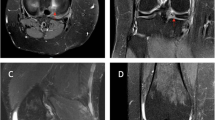

BMSCs reduced microglial activation in the spinal dorsal horn in the rat model of noncompressive disk herniation

Western blotting was used to analyze changes in Iba-1 expression in damaged spinal cord tissue harvested 10 days after SCI (Fig. 6). The protein expression levels of Iba-1 increased significantly in the NP and NP + BMSC groups compared with those in the sham group (P < 0.05) and the Iba-1 levels in the NP + BMSC group were significantly decreased compared with those of the NP group (P < 0.05). BMSC treatment downregulated the protein levels of Iba-1. Consistent with the Western blots, Iba-1-positive microglia were evenly distributed on both sides of the dorsal horn of the spinal cord of rats in the sham group by immunohistochemistry (Fig. 7a, b). Compared with the sham group, the proportion of Iba-1-positive microglia in the NP and NP + BMSC groups was significantly higher on both sides of the dorsal horn of the spinal cord. As reported in previous studies, the application of NP on the L5 DRG could upregulate Iba-1-positive microglia on both sides of the dorsal horn (Xue et al. 2014). In the NP + BMSC group, the proportion of Iba-1-positive microglia was significantly lower on both sides of the dorsal horn of the spinal cord than observed in the NP group (Fig. 7c–f). The intrathecal injection of BMSCs downregulated microglial activity in the dorsal horn of the ipsilateral and contralateral spinal cord in a rat noncompressive disk herniation model (Fig. 7g).

The microglial activation in ipsilateral and contralateral sides of the dorsal horn 10 days after surgery. The red Iba-1 was the marker of the activated microglia. a, b Sham group (ipsilateral side (a), contralateral side (b)); c, d NP group (ipsilateral side (c), contralateral side (d)); e, f NP + BMSCs group (ipsilateral side (e), contralateral side (f)). g Fluorescence intensity data of Iba1 in ipsilateral and contralateral spinal cord horn. *P < 0.05 vs. sham group; #P < 0.05 vs. NP group. The result was mean ± SD of six rats